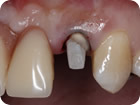

Instalação de Pino de Fibra

Instalação de Pino de Fibra 1

Instalação de Pino de Fibra 2

Instalação de Pino de Fibra 3

Instalação de Pino de Fibra 4